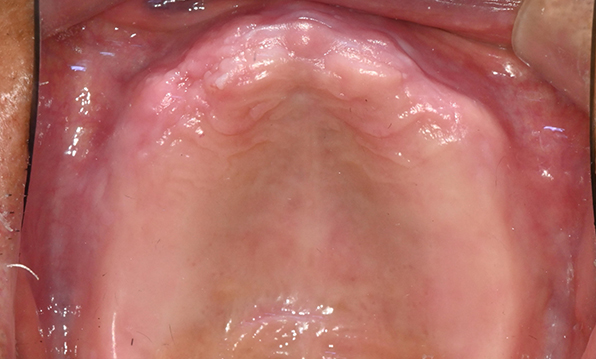

잇몸뼈 충분히 이식 후 임플란트 식립

성공을 위한 노하우, 잇몸뼈 재건 기술

전체 임플란트를 해야하는 환자들은

대부분 고령의 환자들로 오랜 틀니 사용

또는 노화로 인해 치조골이

거의 남아있지 않는 경우가 많습니다.

이 때, 치조골 이식을 병행하여 잇몸뼈 재건 후 안정적인 임플란트 식립을 하고 있습니다.

치료기간 : 2021.04.12~2021.09.15